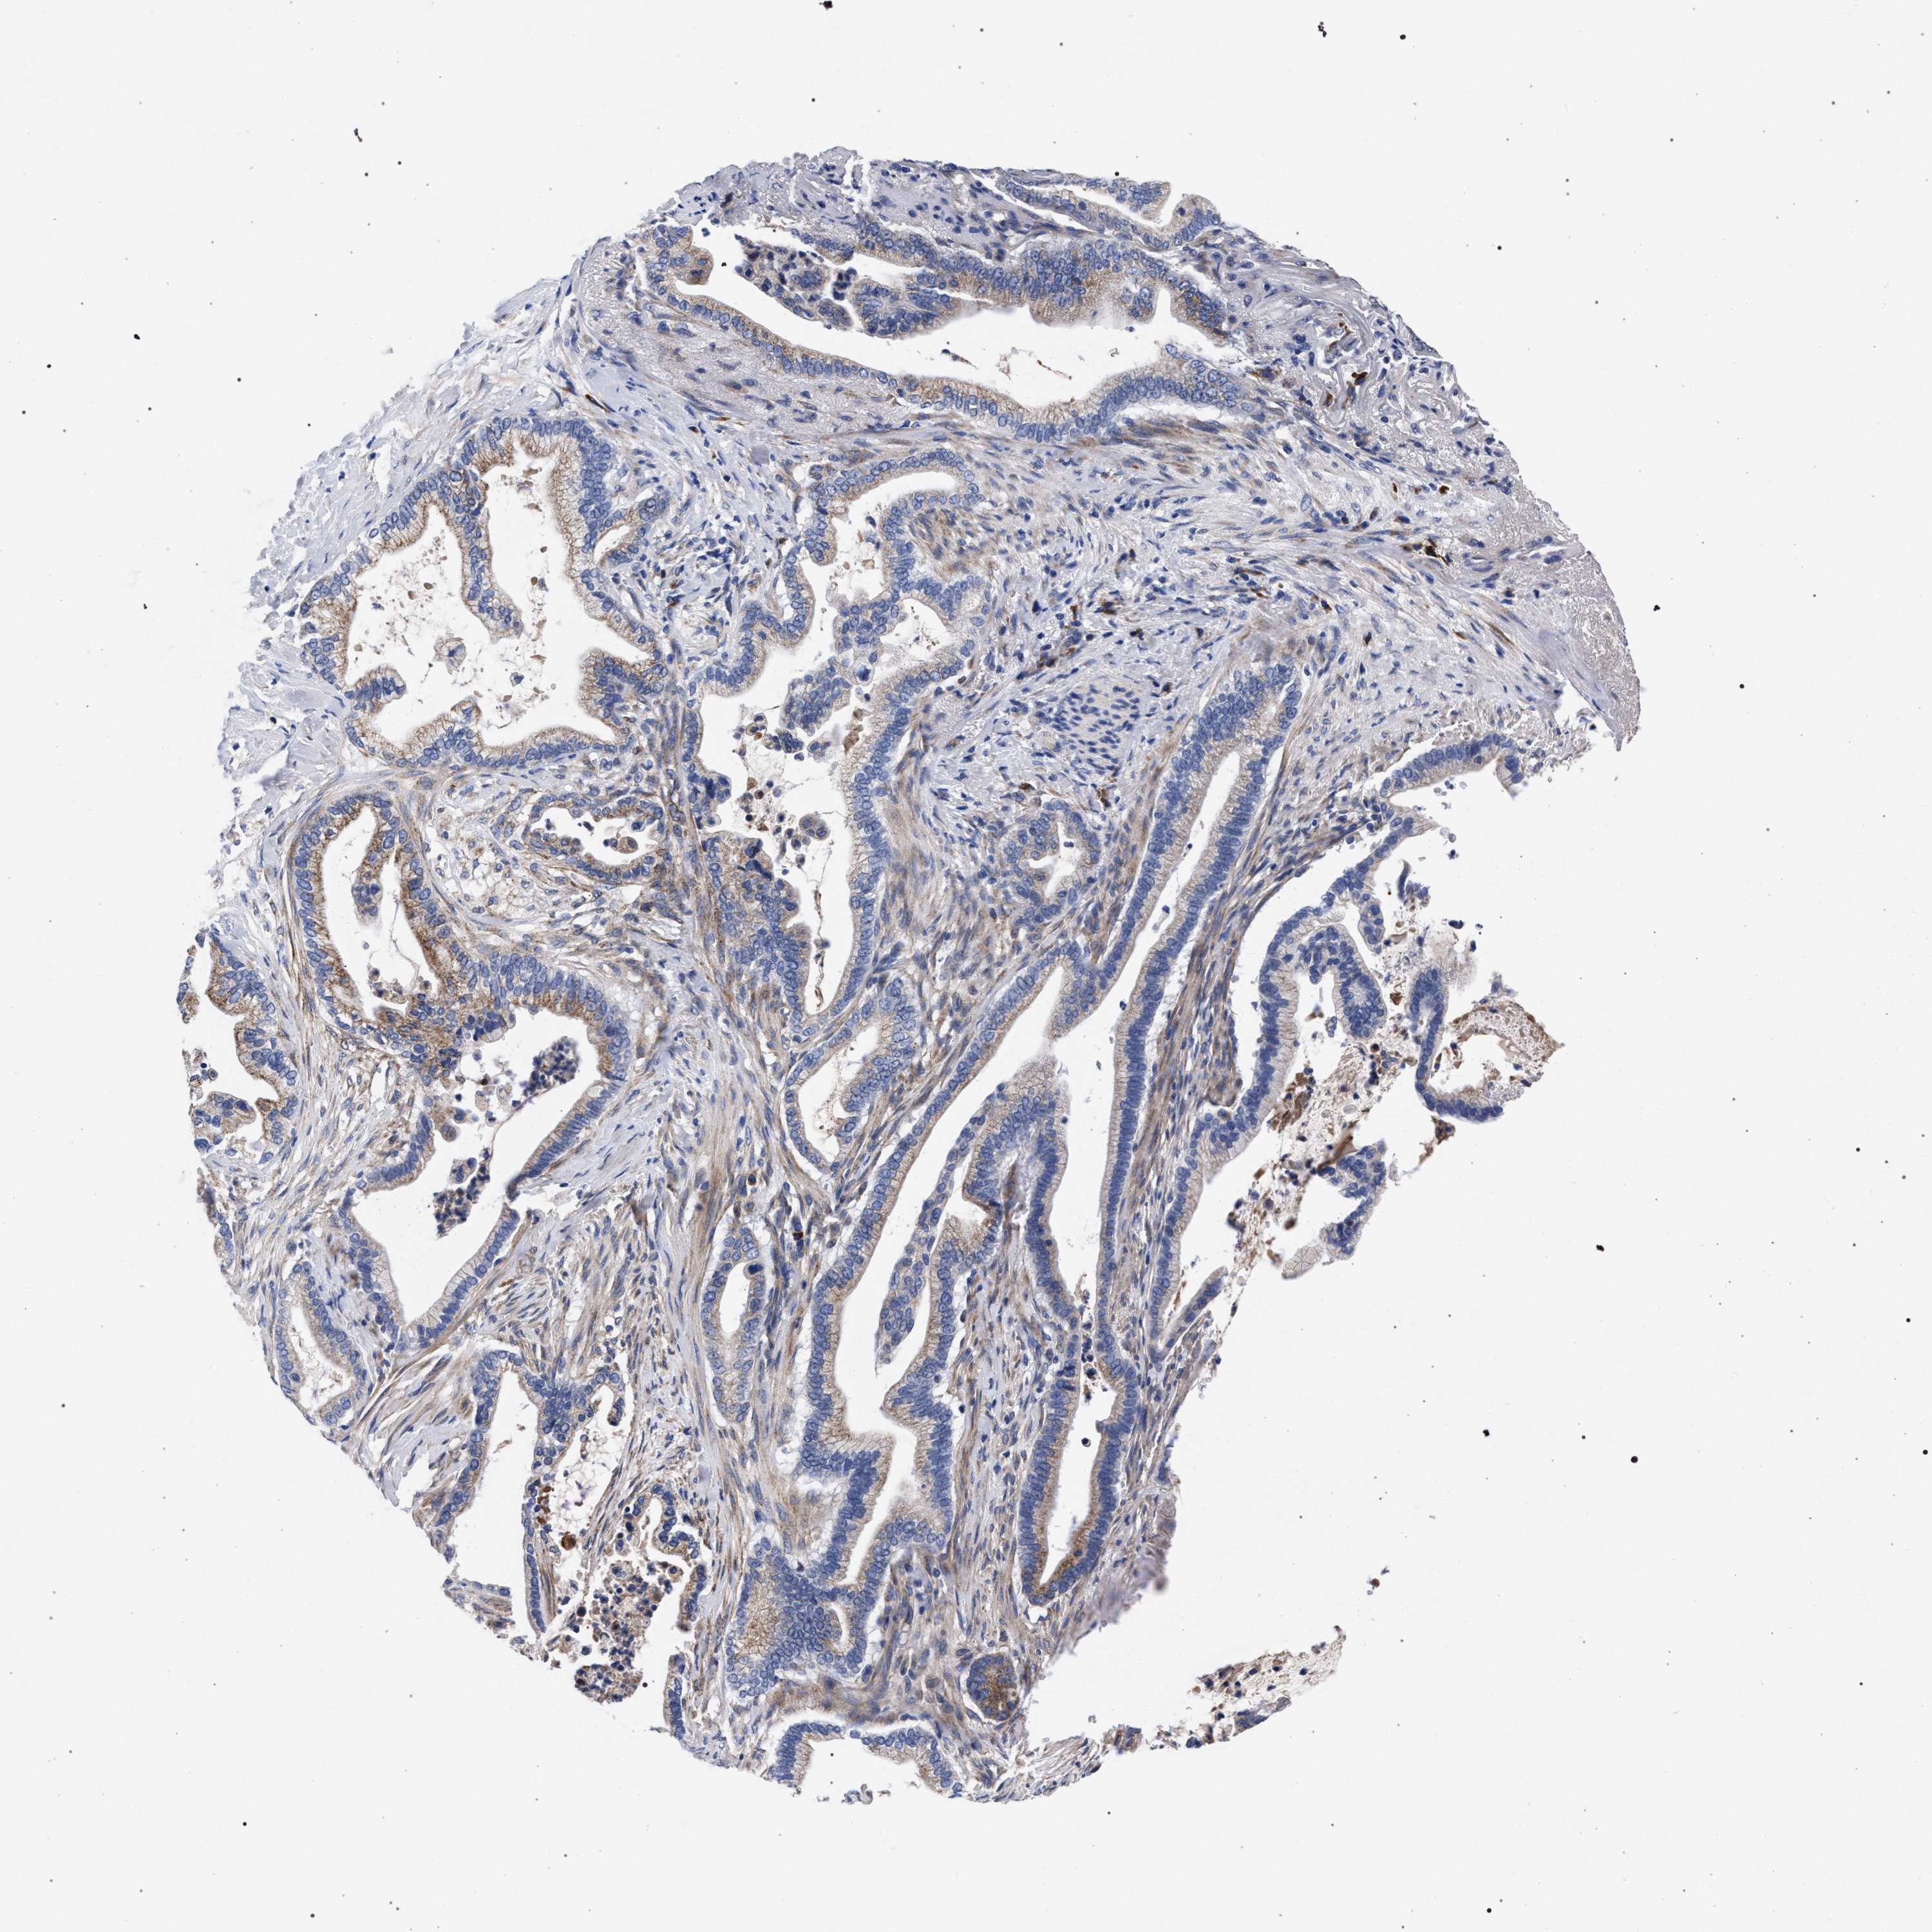

PANCREATIC CANCER - Protein expressioni

A mouse-over function shows sample information and annotation data. Click on an image to view it in a full screen mode. Samples can be filtered based on level of antibody staining by selecting one or several of the following categories: high, medium, low and not detected. The assay and annotation is described here.

Note that samples used for immunohistochemistry by the Human Protein Atlas do not correspond to samples in the TCGA dataset.

Antibody stainingi

Antibody staining in the annotated cell types in the current human tissue is reported as not detected, low, medium, or high, based on conventional immunohistochemistry profiling in selected tissues. This score is based on the combination of the staining intensity and fraction of stained cells.

Each image is clickable and will lead to virtual microscopy that enables deeper exploration of all samples and also displays staining intensity scores, fraction scores and subcellular localization as well as patient and tissue information for each sample.

Antibody HPA021192

Antibody HPA021195

Antibody HPA028759

Antibody CAB021094

Staining

High

Medium

Low

Not detected

Intensity

Strong

Moderate

Weak

Negative

Quantity

>75%

75%-25%

<25%

None

Location

Nuclear

Cytoplasmic/membranous

Cytoplasmic/membranous,nuclear

Adenocarcinoma, NOS

Adenocarcinoma, metastatic, NOS